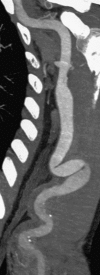

True peripheral artery aneurysms proximal to a longstanding arteriovenous fistula is a well-recognized complication. Late aneurysmal degeneration is rare. This study analyzed the characteristics, therapeutic options, and outcomes of true donor brachial artery aneurysms (DBAA) after arteriovenous fistula (AVF) for hemodialysis. We retrospectively collected the data of patients with DBAA after AVF creation, surgically repaired between January 2001 and September 2015. We excluded patients with pseudoaneurysms, anastomotic aneurysms, and infected aneurysms. We recorded patient's demographics, type of access, aneurysm characteristics, symptoms, treatment, and follow-up. Ten patients were treated for aneurysmal degeneration of the brachial artery. Average aneurysm diameter was 37.5 mm. All cases had, at least, one previous distal AVF, ligated or thrombosed, at the time of diagnosis. The first access was created in mean 137 months before the diagnosis of DBAA. Nine patients had previous medical history of renal transplant and were under immunosuppressive therapy. All patients were symptomatic at the time of diagnosis. In all cases, the treatment was aneurysmectomy followed by interposition bypass. One patient developed a postoperative hematoma with the need of surgical drainage. At 50 months of follow-up, one patient was submitted to percutaneous angioplasty due to an anastomotic stenosis. No other complications occurred during the entire follow-up period (mean: 69 months). The pathogenesis underlying DBAA remains unclear. Increased blood flow after AVF creation, immunosuppressive therapy, and ligation/thrombosis of the AVF may contribute to aneurysm formation. Surgical treatment by aneurysmectomy and bypass, with autogenous conducts, is a safe and effective option.